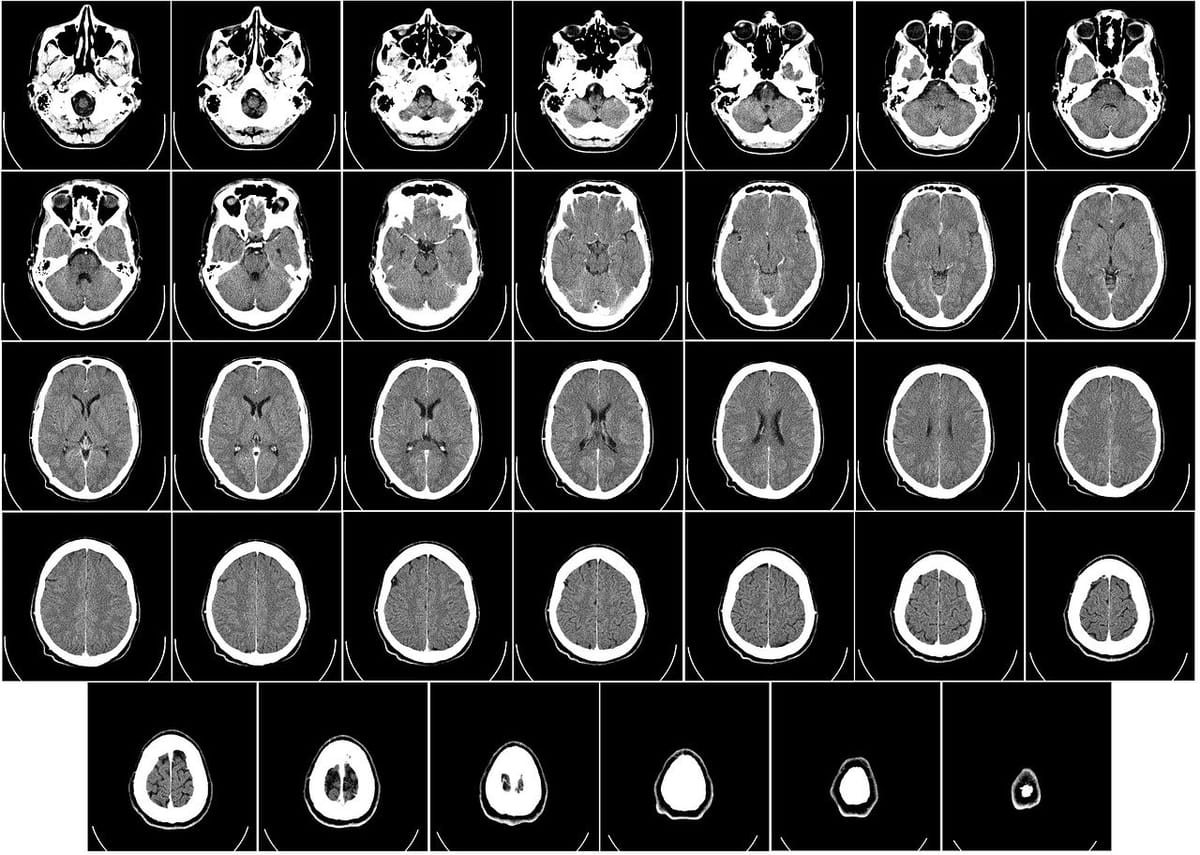

The dark history of medical illustrations

Lucy E. Hyde They were pregnant. Some were prisoners. Others were the poorest of the poor, forgotten in death as in life. Yet dissection and depiction of their bodies have become the foundation of anatomical teaching. Cradled in the pages of...